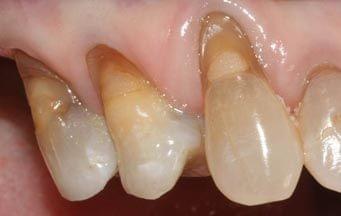

- Sensitive Teeth - Sensitive teeth can impact your eating experience. It is important to determine its exact nature and receive treatment as soon as possible.  - Gum recession - Gum recession is mainly caused by periodontal disease, aggressive brushing and/or use of abrasive products. When gums recede, roots will be exposed and they can be very sensitive to temperature and pressure. Continuous hard brushing can exaggerate the sensitivity and makes it harder to be managed conservatively.  - Tooth decay - Tooth decay exposes inner structure (dentine). When bacteria gets closer to the nerve tissues, hot/cold things can be directly conducted and amplify the sensations, thus causing sensitive teeth.  - Grinding/clenching (bruxism) - Grinding your teeth can wear them down and even cause the teeth to flex along the gum line (abfraction). Continuous grinding habit can cause many dental complications on the long term.  - Dental erosion/erosive wear - Dental erosion is usually caused by an acidic diet (alcohol, soft drinks and citrus) and gastroesophageal reflux disease (GERD). Since the acid will corrode the teeth, inner structure (dentine) will be exposed and cause dentinal hypersensitivity. Placing fillings on erosive wear can be difficult and they tend to last shorter.